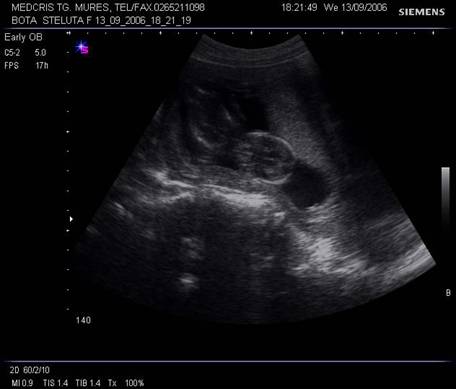

Fig. nr. 20. Sarcina 10 sapt. ecografie transvaginala (se observa aparitia punctelor de osificare ale coloanei vertebrale)

Fig. nr. 21. Aceeasi sarcina de 10 sapt., la ecografia abdominala